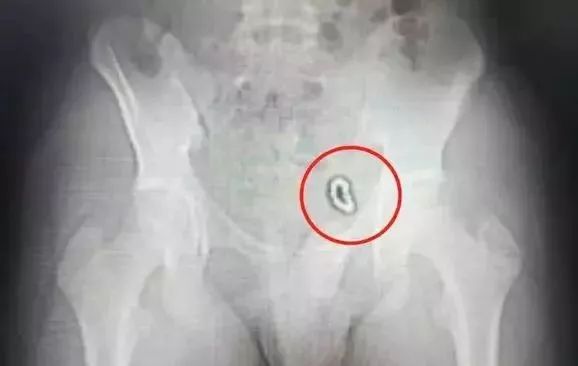

3岁女童丫丫(化名)在玩耍时,无意间把一枚螺丝钉塞进了自己的阴道!并无疼痛,也无流血。丫丫家人发现螺丝钉不见后,焦急万分,立即带丫丫来安徽省妇幼保健院东区就诊。

在B超提示下,医生很快发现了丫丫阴道内的异物。

在短短的3分钟内,一枚长达2.5厘米的螺丝钉取出来了,手术室的医护人员都长长地吁了一口气。经过一夜的视察后,丫丫第二天便出院了。

拍完X光片后发现:小浩下腹部左侧像是挂了一道环形“手串”,10多颗珠子紧紧连在一起,固定在膀胱左侧壁。